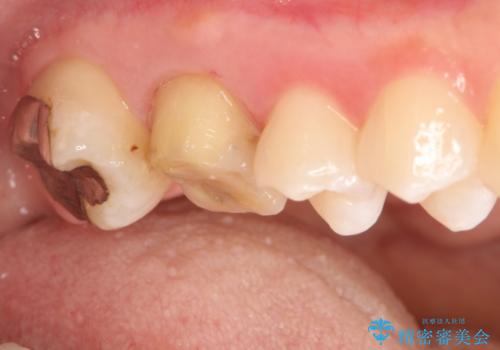

- 右上の歯茎が腫れてきたとのことで来院されました。

右上6番目の歯の位置に腫脹があり、膿も出ている状態でした。

レントゲンを撮影すると、根の先端から膿が排出されていることがわかりました。

根の神経の治療を行い、セラミックを装着する計画としました。